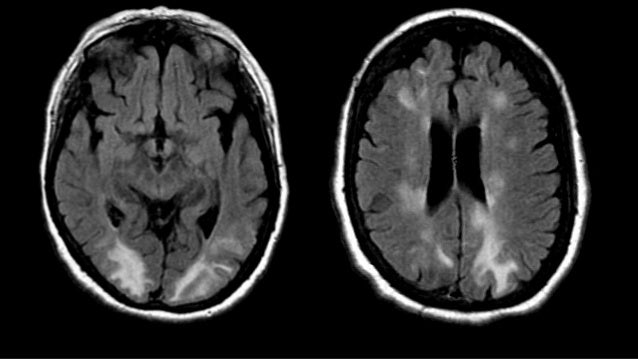

Enfermedad De La Sustancia Blanca Imagenologia

Leucoencefalopatia Posterior Reversible Descripcion De Dos Casos Asociados A Vincristina Anales De Pediatria